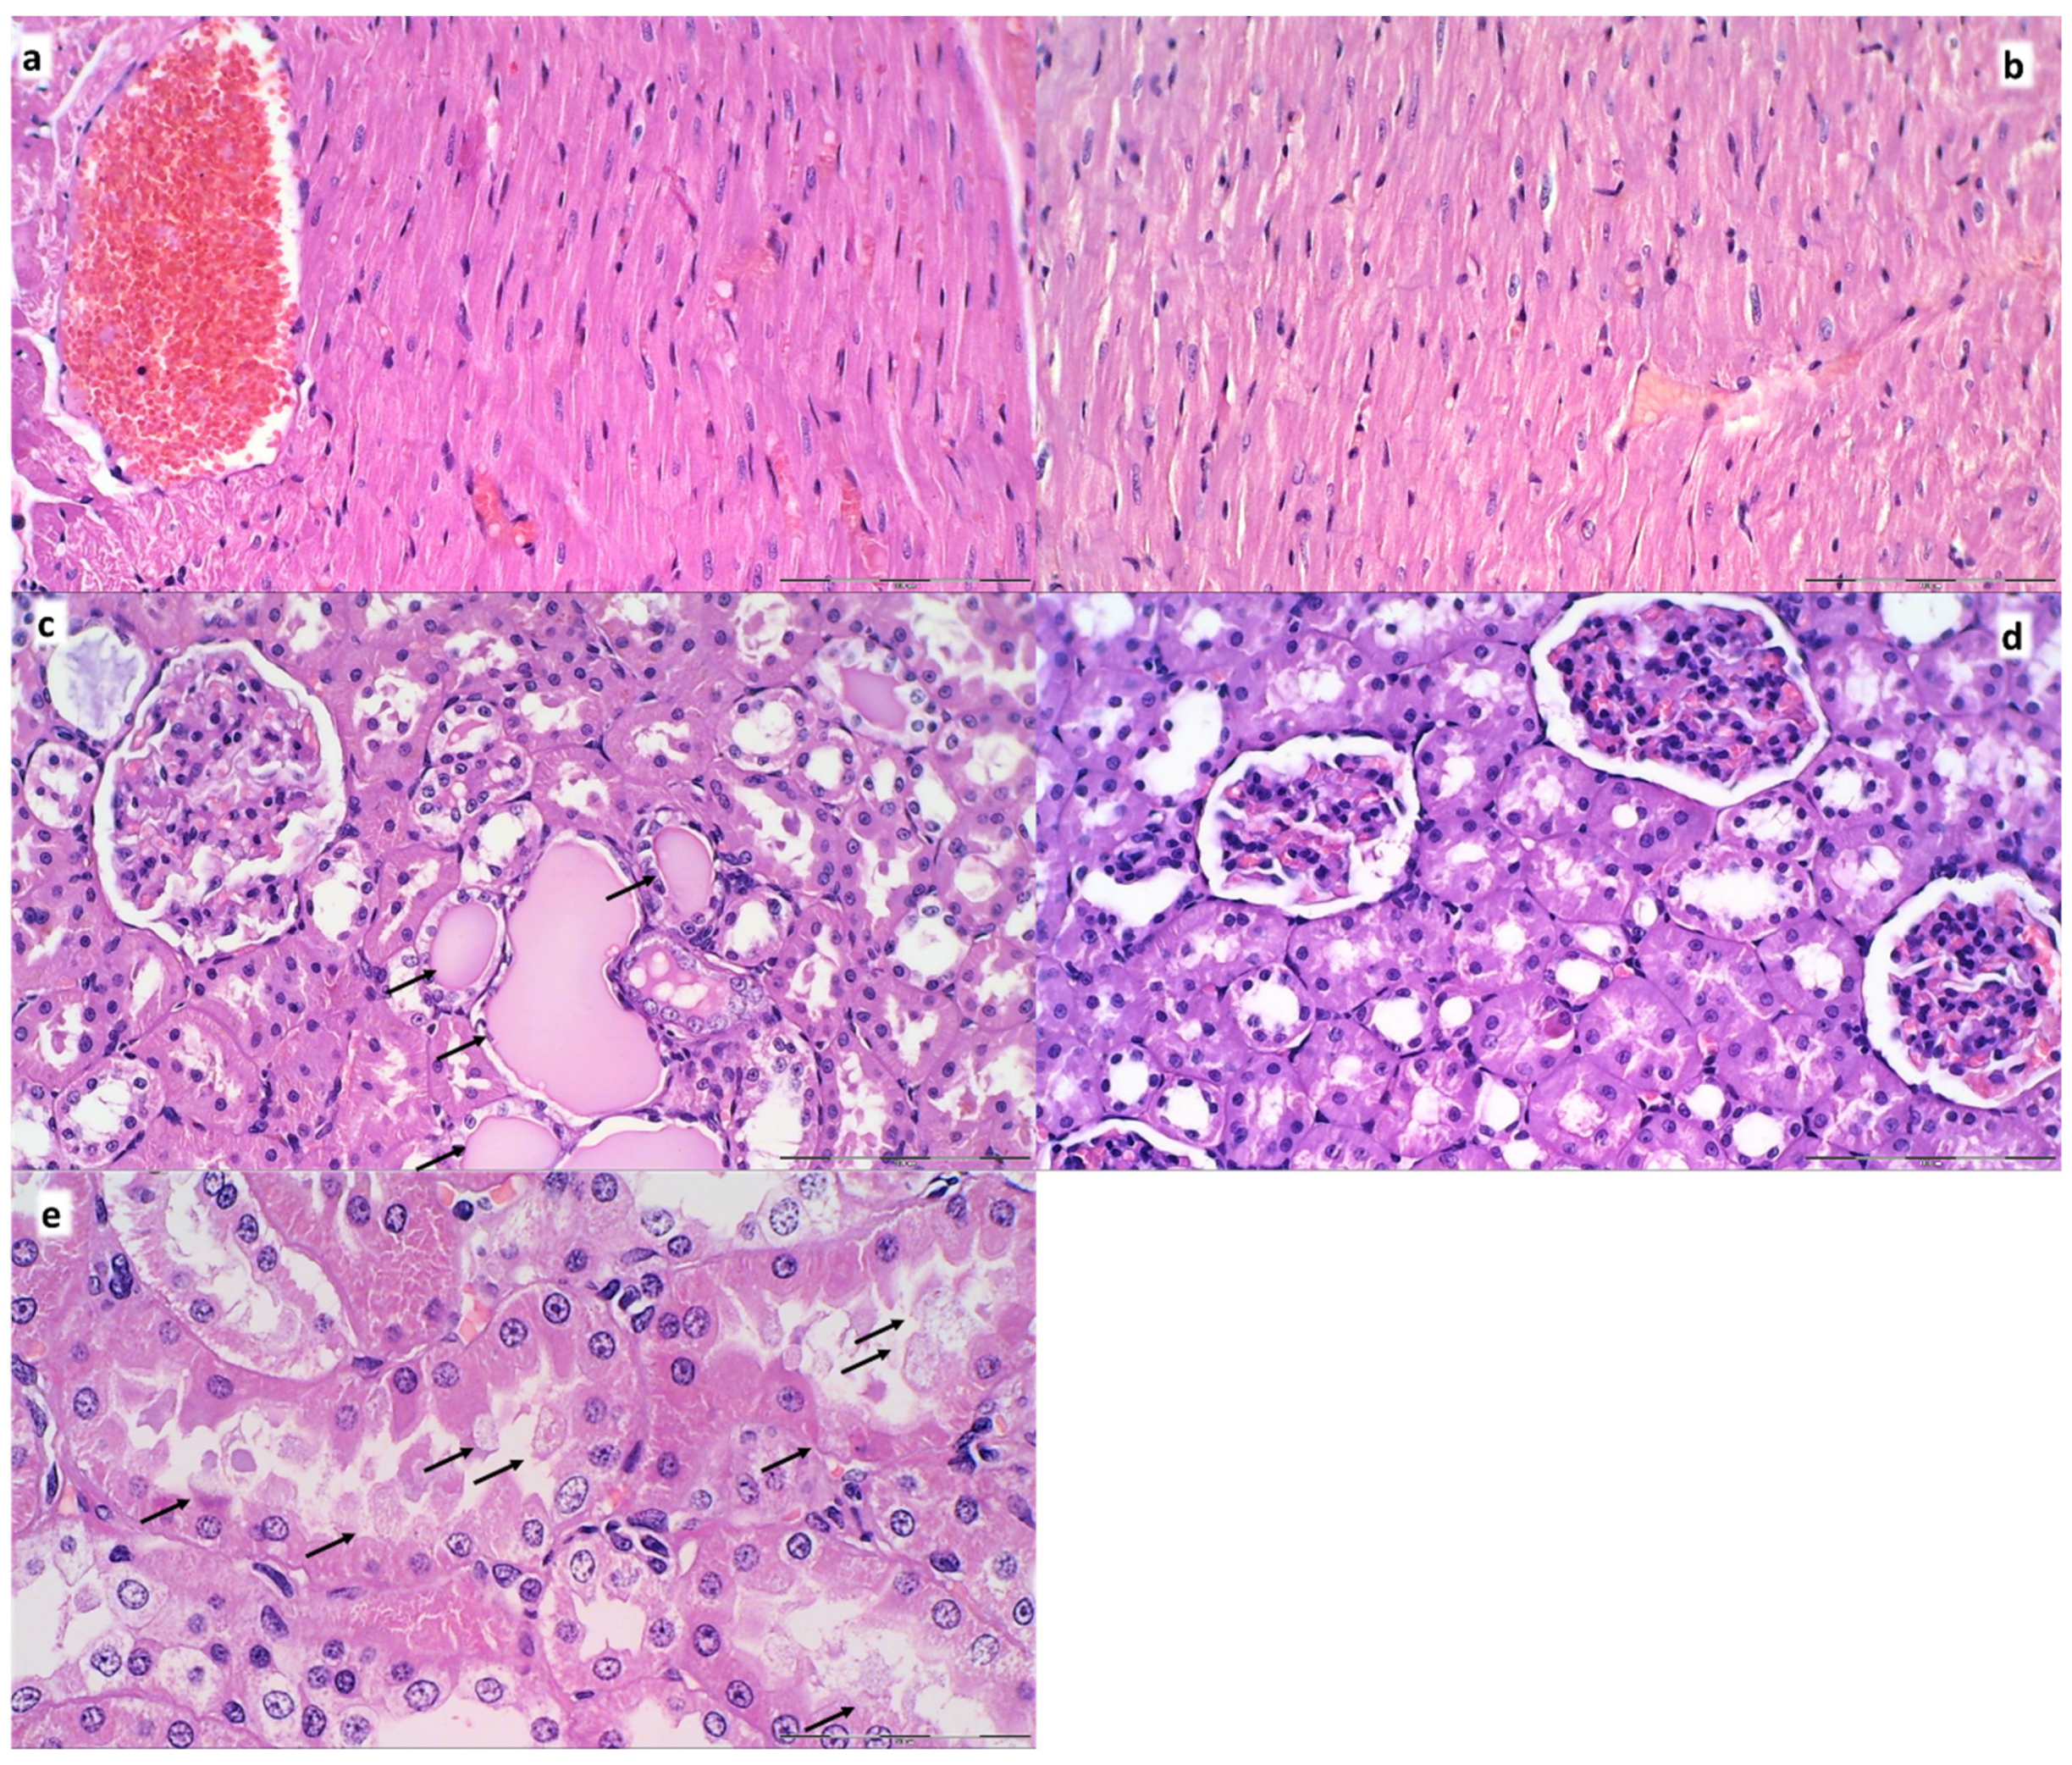

3.9. Histology